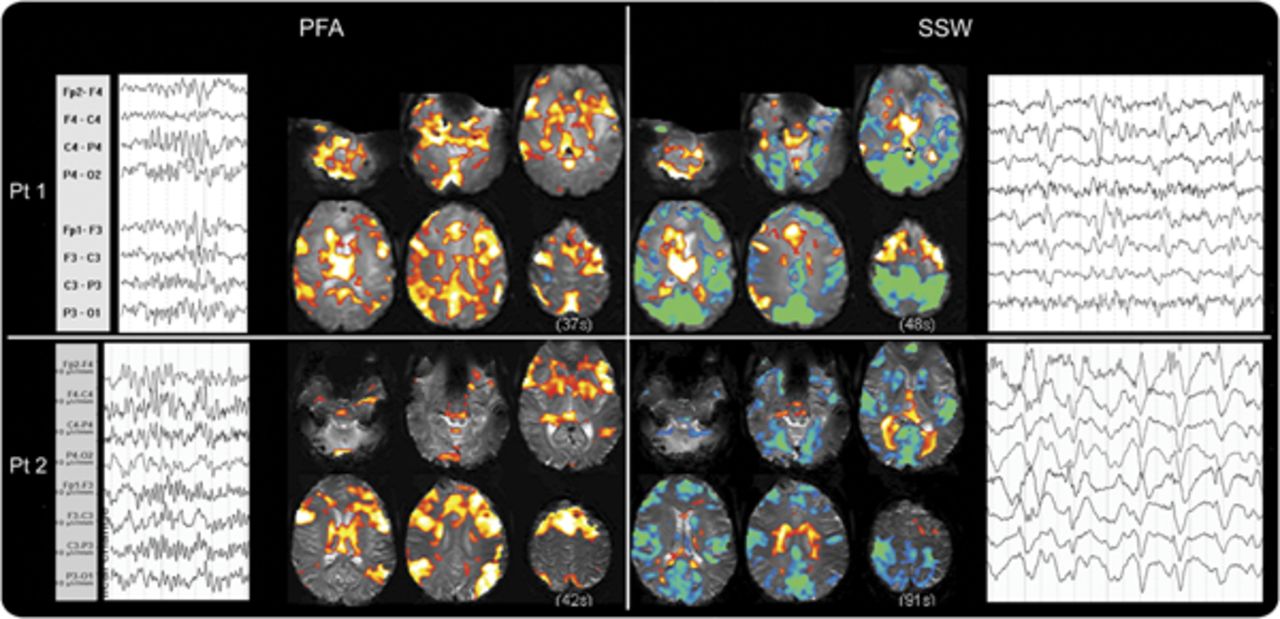

良好的样本PFA和量都记录在2主题,和这两个人演示模式的基本特征在整个集团(图3)。

在所有患者6 PFA,皮质大胆的改变几乎完全是积极的信号。外显率的分布地图显示激活(图2一个;个案如图e 1上首页®网站www.首页neurology.org)。PFA-related大胆的增加主要影响广泛的额叶皮质“协会”地区,顶叶枕叶和颞叶,但似乎并没有意识到涉及初级皮层。

结合阈值SPM PFA的“外显率地图”(A)和(B)西南偏南约显示大脑皮层和皮层下的整体模式的激活和解除激活这些癫痫样的事件。颜色代表对象的数量规模与显著激活体素(黄色高于阈值的像素点为所有6科目PFA和9 f)。增加在大胆的信号显示在暖色和冷色的减少。没有大胆的反应主要在PFA皮质;初级运动、视觉和听觉皮层(箭头)没有激活或不激活体素,而所有这些领域显示减少大胆在f(同样的箭头在B)。在联合皮质(例如,箭头在顶叶皮层)强烈激活在量和没有大胆的在量的变化。这是真的协会地区除了一些地区的额叶皮质显示量的失活。皮层下结构,如脑干和尾状,显示激活量在PFA和失活。尽管个人更多的变化结果与量覆盖所有情况下导致这种识别的模式。大胆=血氧等级相关;PFA =阵发性快速活动; SPM = Statistical Parametric Mapping; SSW = slow spike and wave.

缓慢的上升和波。

量排放记录9例。他们与正面和负面的皮质大胆的混合信号的变化(图2、e 1和飞行)。

不像PFA,皮质是西南偏南约模式变量(图飞行)。的一部分,这可能是由于有限的数据量(患者9、10、13)。患者6,7,8弱难以解释的激活。患者1、2和5有强烈激活外显率最佳解释的引用映射(图2)。这表明失活往往是在初级皮质(电动机、视觉和听觉)和中线顶叶皮层。有分散在其他领域积极激活皮层,特别是额叶皮层的某些地区。

我们的研究的主要发现是PFA和f (LGS)的2定义电记录的特性有独特和明显不同的大脑皮层和皮层下大胆的信号变化模式。PFA显示了一个独特的、分散和一致的“激活”,大脑的许多地方,特别是在协会皮层(图2)。

PFA显示激活在广泛领域的皮层,但似乎备用主皮质。PFA显示增加大胆信号的皮层下结构包括丘脑、基底神经节,和脑干,所有已知的“联合皮层有广泛的联系。“这观察激活在许多领域与协会有关皮层和皮层下系统,但不包括初级皮层,导致我们称之为网络激活,我们看到在PFA”扩散协会网络激活”(DANA)。此外,在大多数情况下,不同的左/右或前/后头皮排放的重点体现在前/后招聘比例左/右或分散的网络。